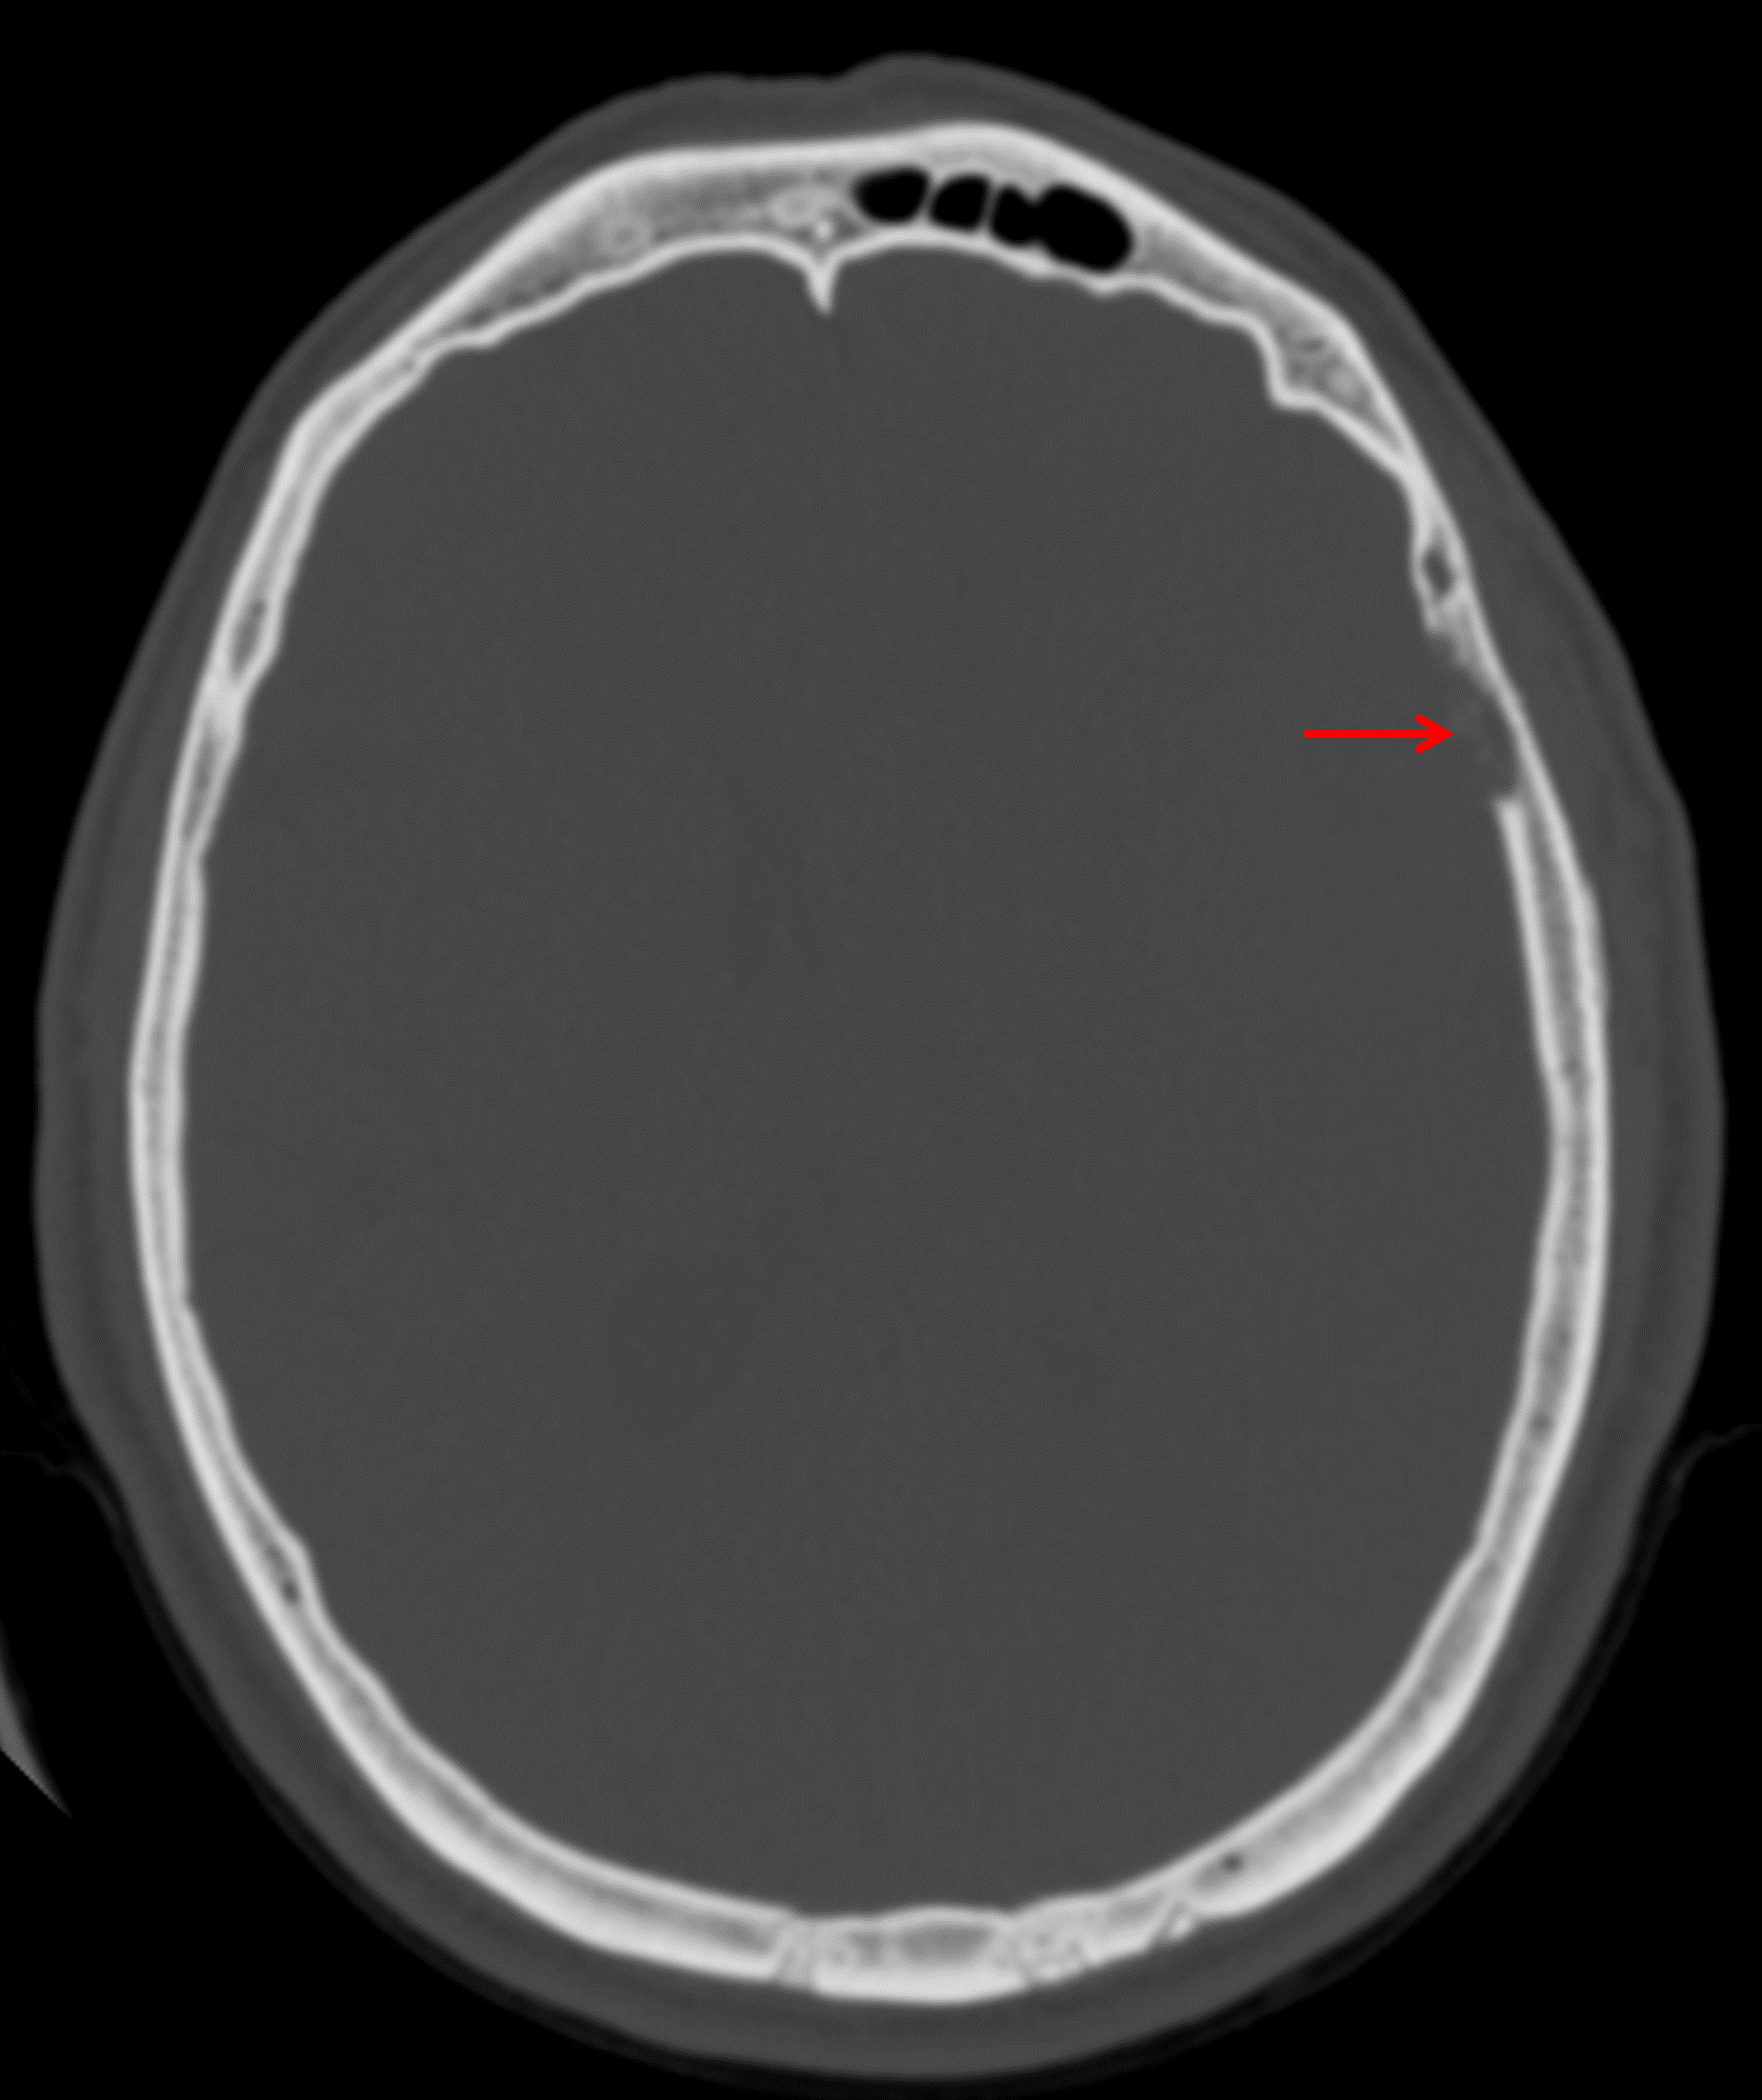

Age: 51

Sex: Male

Indication: Headache

CT

Solitary fibrous tumor (hemangiopericytoma)